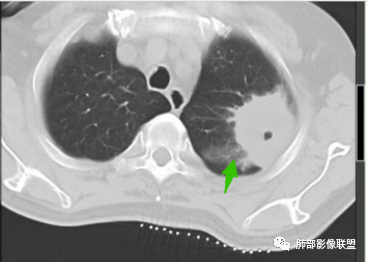

厚壁空洞,内壁光滑,内部液化坏死

厚壁环形强化明显

有气泡

考虑慢性脓肿形成

3.CT表现:肺脓肿可呈结节状或团块状,有时呈不规则形,气道来源肺脓肿常单发,血行来源常多发,边缘模糊,部分病灶周围可见片状肺实变及磨玻璃影;病灶中央为液化坏死区,若脓肿与支气管相通,脓液排出可形成空洞,空洞内可形成液平;急性肺脓肿内壁多不规则;慢性肺脓肿洞壁较厚,一般不规则或形成多房空洞:CT增强扫描空洞壁可见强化,空洞壁为纤维肉芽组织,呈典型的环形强化;慢性肺脓肿周围可有较广泛的纤维索条影,可伴支气管扩张、肺气肿或胸膜增厚表现。

何家伟老师的精彩分析本例指向慢性肺脓肿主要有以下几点:1.患者病史长,白细胞不高,无发热,病程中有浓痰;2.慢性肺脓肿多为厚壁空洞,邻近肺野可见慢性肺炎、长纤维索条影;3.本例厚壁空洞,明显均匀环形强化,外壁见不规则棘突,未见明显分叶毛刺;内壁光滑,有完整强化环,无凹凸不平及壁结节等;4.空洞厚壁中可见血管穿行,未见破坏侵犯征象;5.邻近胸膜呈糊墙改变,胸膜下脂肪间隙清晰,未见侵犯,倾向炎性改变;6.空洞内可见液化坏死及气体,非凝固性坏死、干酪性坏死;7.纵隔及肺门未见肿大淋巴结。